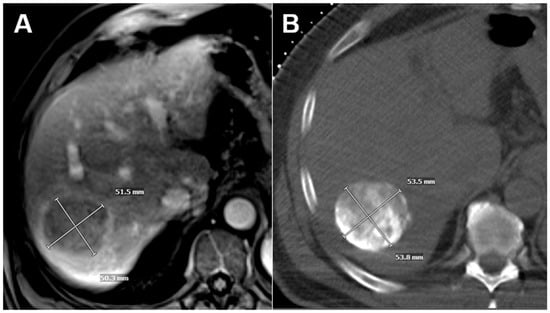

Intraprocedural imaging used for follow-up tumoral measurements consisted of contrast-enhanced or non-contrast intraprocedural cross-sectional imaging, either CT as part of a combined angiography/CT suite or cone-beam CT with axial reconstructions. Intraprocedural contrast-enhanced cross-sectional imaging was performed prior to embolization to delineate vascular anatomy and tumoral perfusion. Intraprocedural non-contrast cross-sectional imaging acquired after embolization was performed to assess completeness of the embolization procedure via tumoral staining (Figure 1).

Figure 1. Example of an HCC initially measured on contrast-enhanced MRI (A) and then remeasured using tumor staining on intraprocedural non-contrast CT obtained after TAE using a combined angio/CT suite (B).